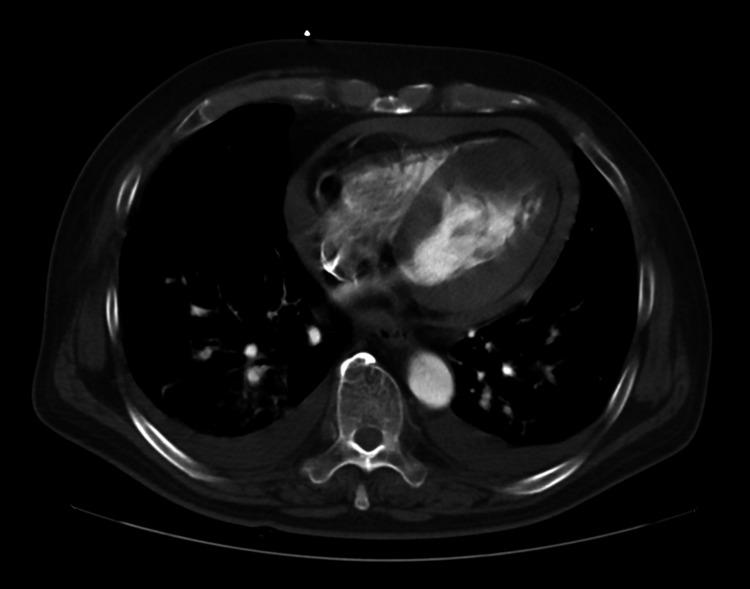

A 66-year-old male patient underwent repair using the sutureless technique for an oozing-type cardiac rupture associated with myocardial infarction of the anterior left ventricular wall. On postoperative day 10, echocardiography revealed a thrombus in the apex region, and anticoagulation therapy was started with warfarin. The thrombus disappeared two months postoperatively. Four months after surgery, the patient came to the hospital with a chief complaint of breathlessness. The computer tomography scan showed a pseudoaneurysm in the left ventricular anterior wall. Because of breathlessness due to decreased effective cardiac output associated with the left ventricular mass and the risk of rupture of the left ventricular pseudoaneurysm, we decided that surgery was indicated. When the left ventricular pseudoaneurysm was incised under cardiac arrest using an artificial heart-lung machine, an oval-shaped communication orifice was found, which was closed directly with continuous sutures. The breathlessness disappeared and the patient was discharged 13 days after surgery.

一名66岁男性患者因左心室前壁心肌梗死伴渗出型心脏破裂,采用无缝合技术进行修复。术后第10天,超声心动图显示心尖区域有血栓形成,遂开始使用华法林进行抗凝治疗。术后两个月血栓消失。术后四个月,患者因呼吸困难为主诉前来医院就诊。计算机断层扫描显示左心室前壁有假性动脉瘤。由于左心室肿块导致有效心输出量减少引起呼吸困难以及左心室假性动脉瘤破裂的风险,我们决定进行手术。在使用人工心肺机使心脏停搏的情况下切开左心室假性动脉瘤时,发现一个椭圆形的交通口,用连续缝合直接将其封闭。呼吸困难消失,患者术后13天出院。